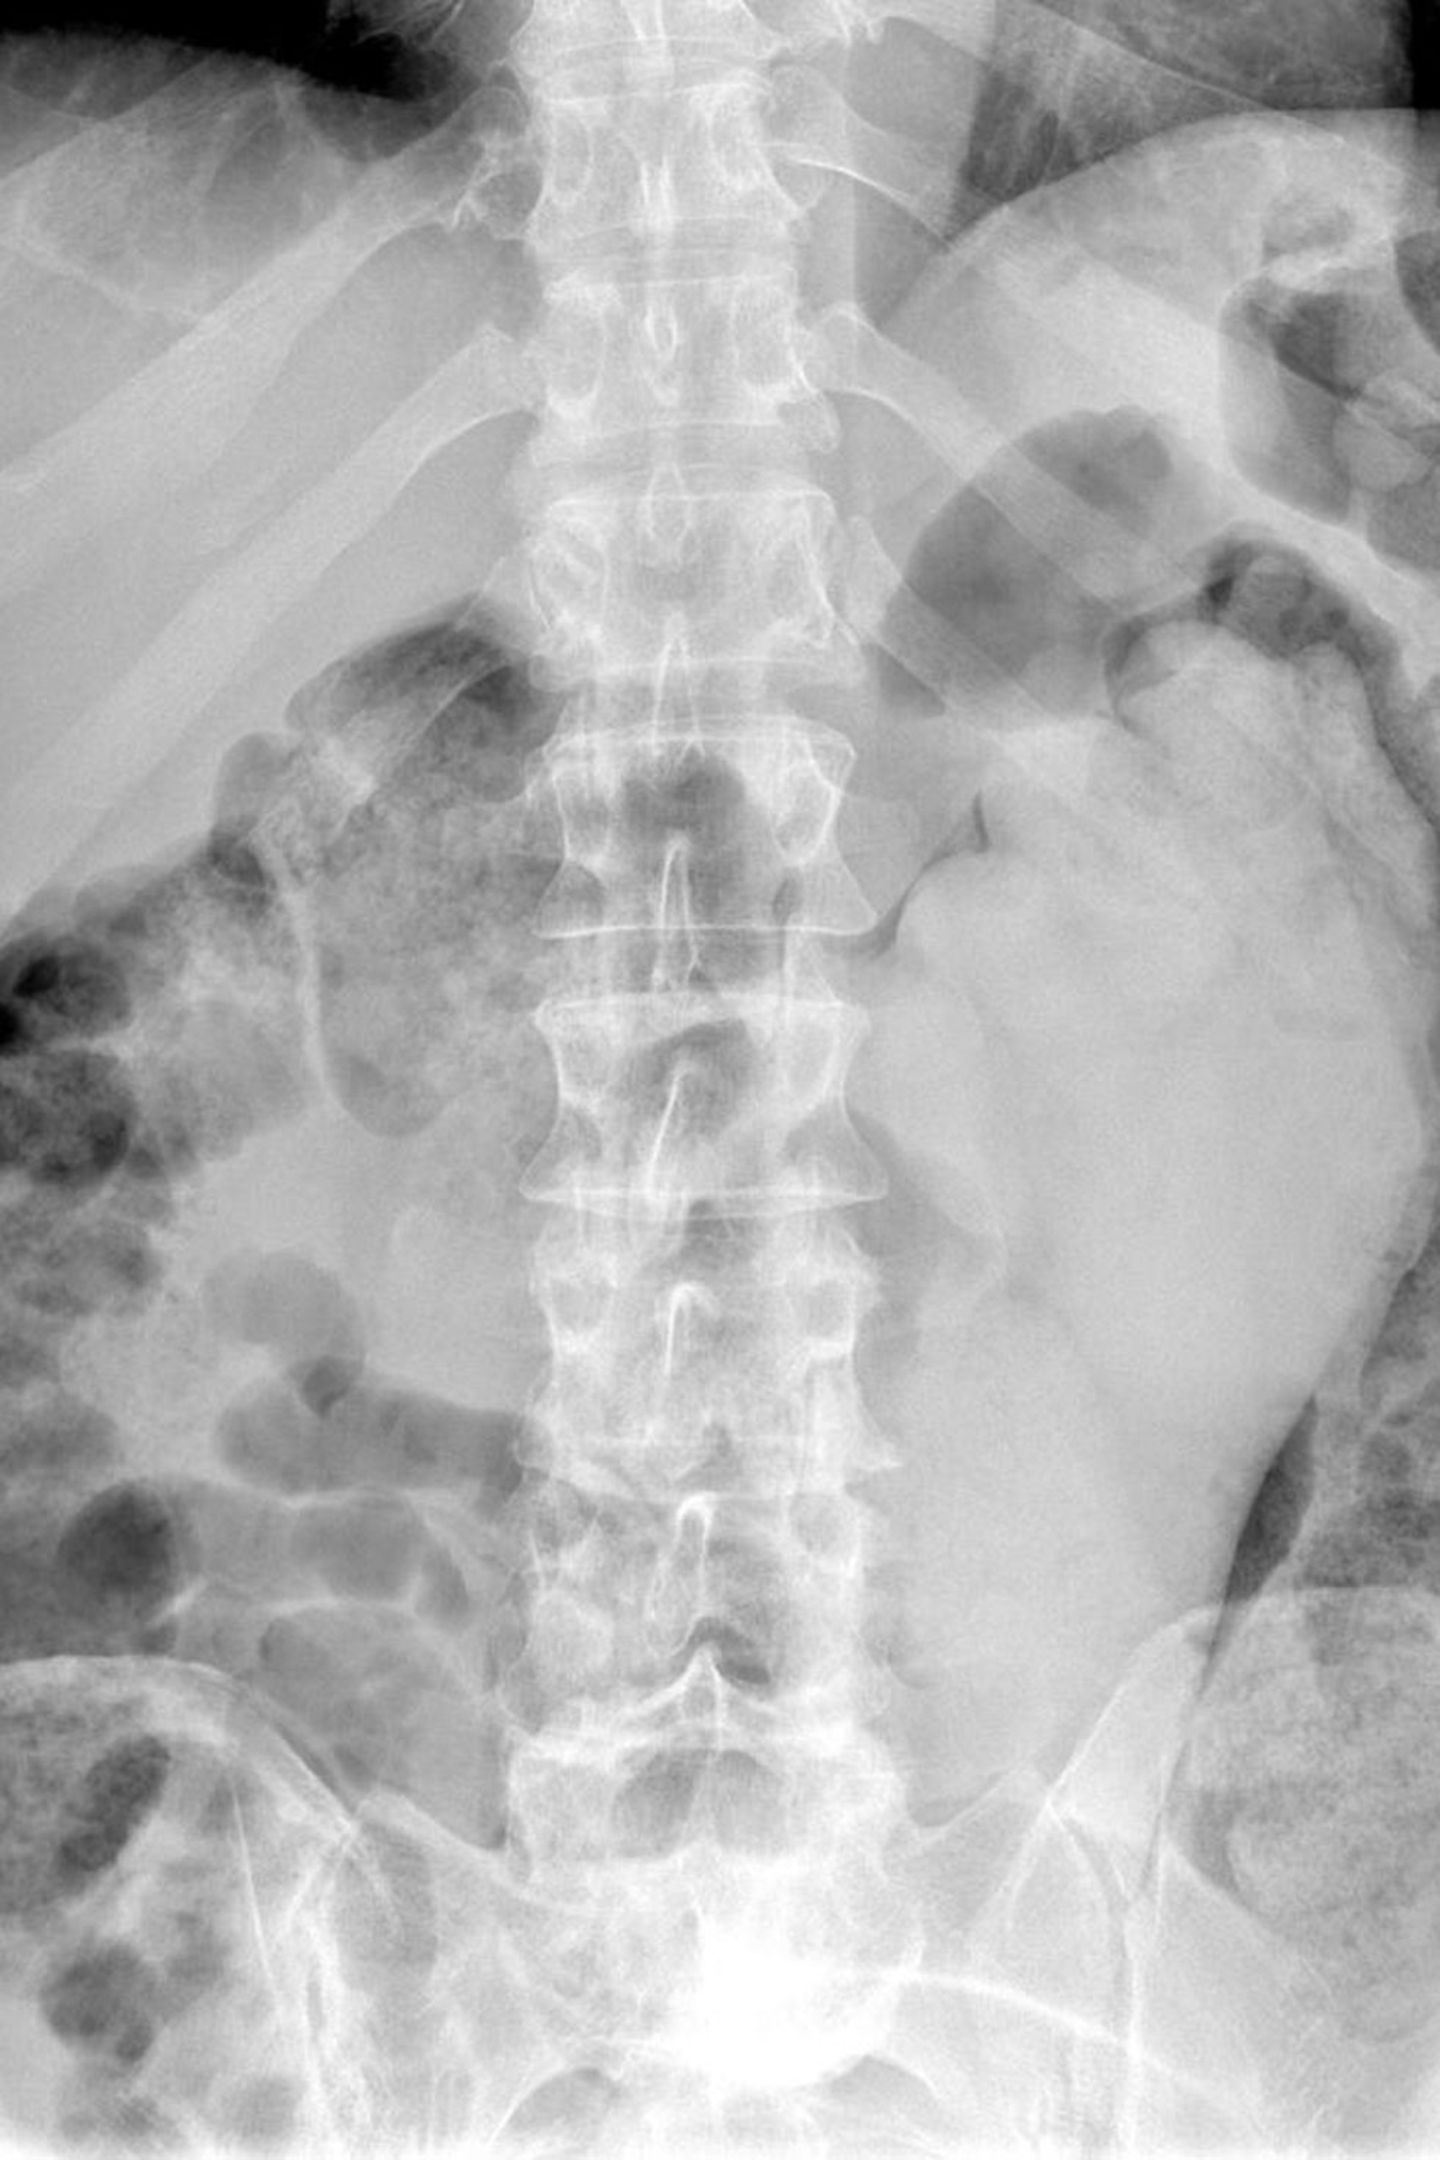

• Vom Dildo bis zur Orange: Was Ärzte auf Röntgenbildern entdecken

Schmerzhaft: Hier hat sich ein Ei im Darm des Patienten verhakt. Dieser hatte es zur sexuellen Stimulation eingeführt. Auf dem Röntgenbild wird sichtbar, wie weit das Ei im Körper steckt.